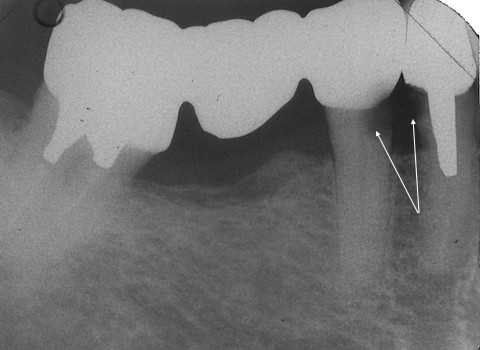

20代男性、咬合性外傷によるカリエス咬合性外傷というのは、歯ぎしり、食いしばり、嚙み鳴らし、硬い食品の嗜好、いつもガムを噛んでいるなどの歯にダメージを与える悪習癖のことだ。具体的にはクラックが入りそこから虫歯になっていく。最悪割れてしまう。前回のつづきhttps://plaza.rakuten.co.jp/mabo400dc/diary/202106210000/今日は左上3の2次カリエスだが、処置には困難を極めた。もう諦めよっかな〜シリーズかと思われたwミラーテクニックしか使えない。直視できないのだ。歯肉縁下2〜3mmはある。切削バーが届かない。露髄して血だらけになった。軟化象牙質除去が十分かの確認が困難。こういう場合、通常治療ではどうか?、想像してみた。治療困難で抜歯か?まあ、歯冠を切り飛ばして、神経を取って差し歯がせいぜいだろう。レントゲン写真で見てもCRがくるくると虫歯の穴の中で回っているのがわかる。この画像を見て歯髄の保存治療ができると思う同業者は少ないと思う。見た目は歯質がたくさん残っているように見えるかもしれないが、内部は伽藍堂。矢印部分が露髄しているところだ。では時系列でどうぞ

20代男性、咬合性外傷によるカリエス咬合性外傷というのは、歯ぎしり、食いしばり、嚙み鳴らし、硬い食品の嗜好、いつもガムを噛んでいるなどの歯にダメージを与える悪習癖のことだ。具体的にはクラックが入りそこから虫歯になっていく。最悪割れてしまう。前回のつづきhttps://plaza.rakuten.co.jp/mabo400dc/diary/202106200001/今日は左上6の再建だ。口蓋遠心咬頭が破折した。しかも歯肉縁下まで破折しているので電気メスで歯肉を切り下げた。歯肉以外には麻酔は効かせていない。患者には申し訳ないが、健全象牙質をセンサー代わりに使った。痛みが出れば健全象牙質なのでこれ以上は削る必要がないと判断できる。前回は神経が取られていたが、今回はそうではない。α-TCPセメントこそ使っていないが、前の先生は頑張ったと思う。レントゲン写真前医のCRを除去すると歯質はほとんど残っていない。前回よりもマシな程度だ。では時系列でどうぞ、、